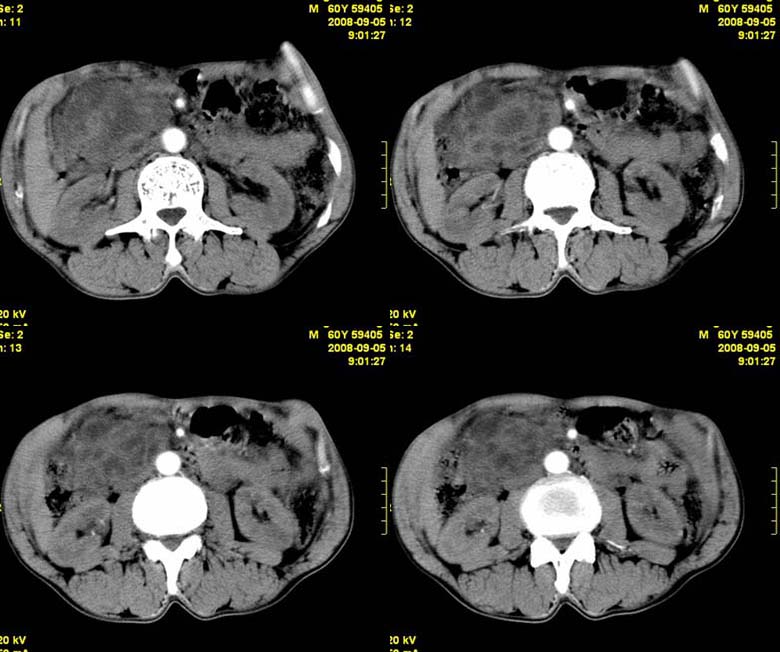

标题: CT15580:M60Y,胰腺病变,平扫+增强 [打印本页]

标题: CT15580:M60Y,胰腺病变,平扫+增强

患者,男, 60,既往有间歇腹痛病史多年,现右上腹痛,加重一月,伴右后背部疼痛,无黄疸,无发热。

胰头囊腺瘤/囊腺癌.

胰腺炎,胰液滞留性假囊肿

考虑胰腺囊腺瘤或慢性胰腺炎。

胰头区增大,胰管明显扩张,不均匀强化,且与 周围结构不清,后背疼痛,考虑为胰腺头部胰腺癌。

胰头囊腺癌

考虑胰腺囊腺瘤或慢性胰腺炎可能性大

粘液性囊腺瘤

同意胰头部囊腺癌

胰头囊样增大不均匀强化,腺管扩张。结合病史首诊慢性胰腺炎、假性囊肿